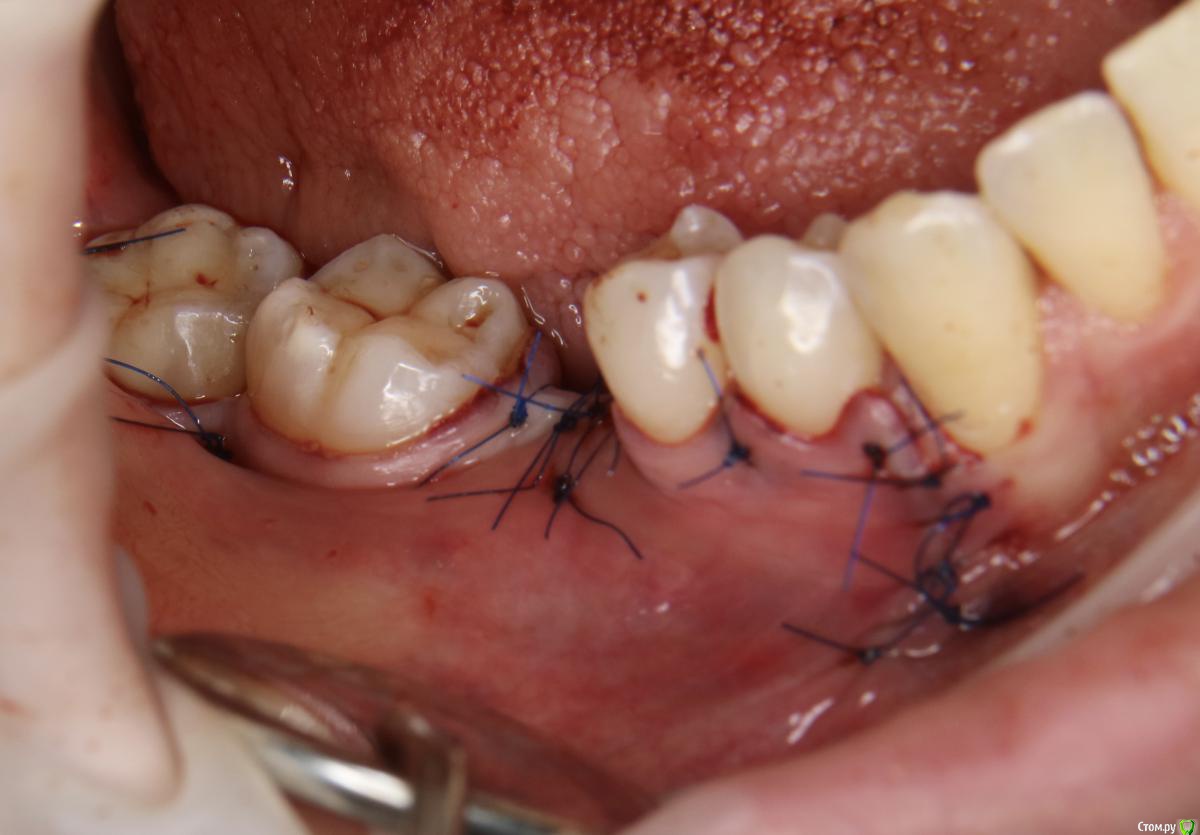

Александр07 Опубликовано 21 августа, 2020 Поделиться Опубликовано 21 августа, 2020 Коллеги добрый день, решил углубиться в тематику костных пластин по Кюри, определенные знания и некоторый опыт есть, небольшой, хотел поделиться последней работой, если какие то советы /замечания есть с удовольствием выслушаю 8 Ссылка на комментарий

Bier Опубликовано 21 августа, 2020 Поделиться Опубликовано 21 августа, 2020 толстый очень ламинат. а так все хорошо ) Ссылка на комментарий